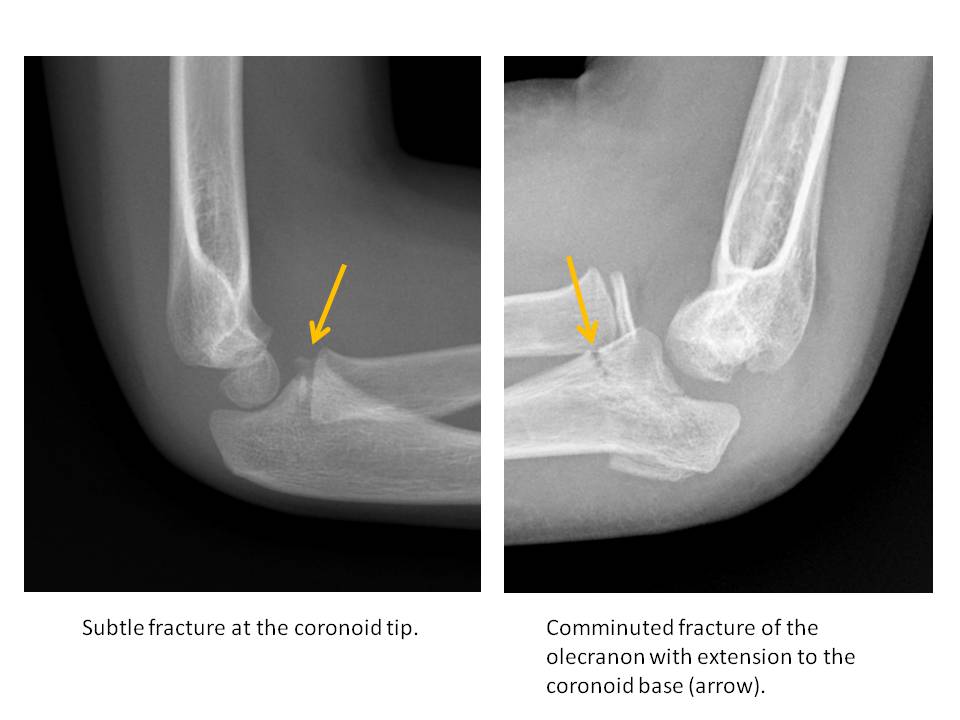

The coronoid process is fractured. [Yes/No]

The olecranon process is fractured. [Yes/No]